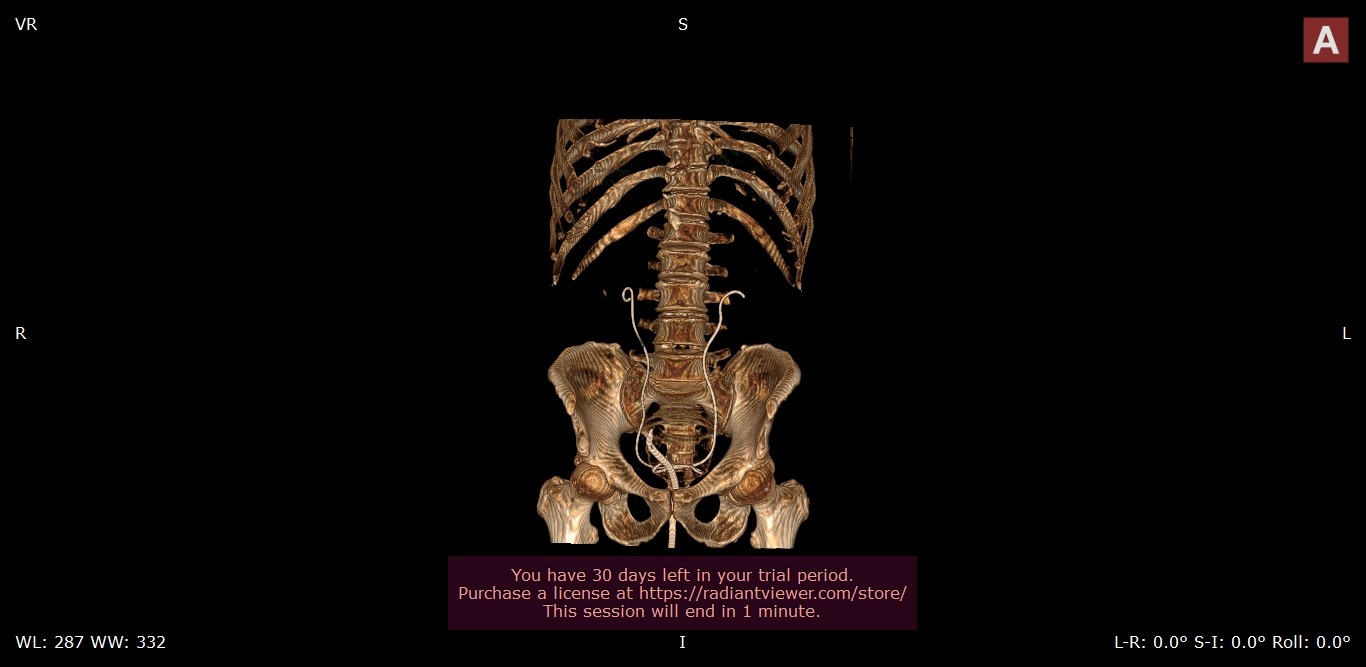

The patient was stable and exhibited signs of recovery following the surgical placement of JJ stents in the kidneys. After 4 days the improvement was evident in the non-contrast control MDCT scans with visualization on double JJ stent in both ureters conducted after the surgical procedure. Moreover, there were no indications of any free fluid in the surrounding kidney tissue.

Figure 5. Visualization of the JJ stents and the placed urinary catheter using 3D volume rendering.